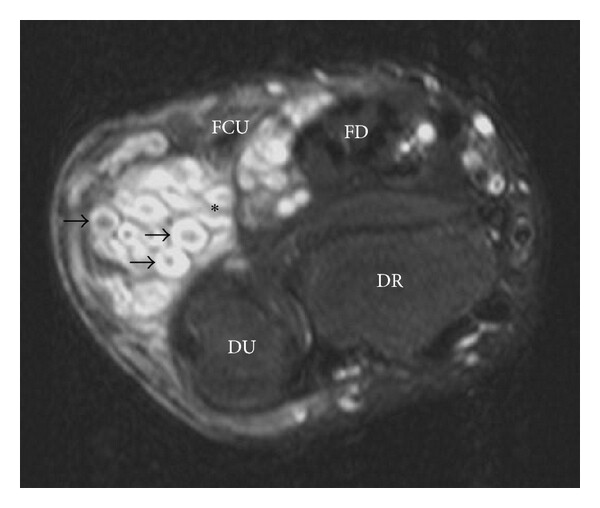

3) Imagen

3.1 RM: prueba principal

- Delimita la extensión real del PN.

- Valora la relación con nervios, plexos, vasos, médula y órganos.

- Permite detectar nódulos dominantes, heterogeneidad y signos de alarma.